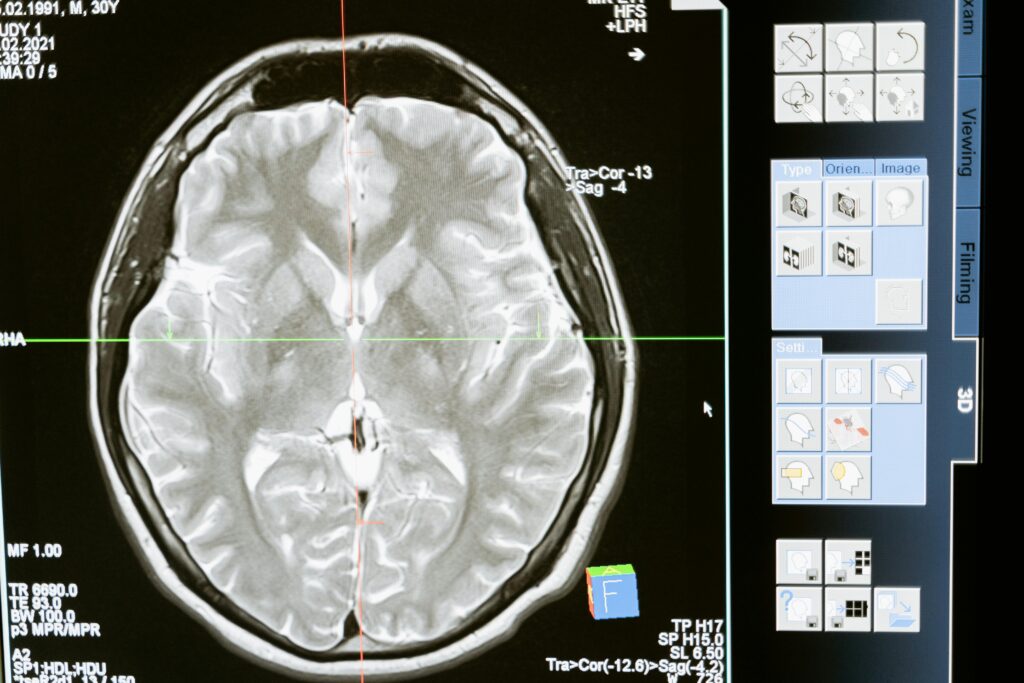

Cuando una persona sufre un daño cerebral adquirido (DCA) – como un ictus, un traumatismo craneoencefálico o una anoxia cerebral – su vida y la de su entorno cambian de forma repentina. En un instante, todo se transforma: la rutina, las capacidades, las prioridades.

El DCA puede afectar a funciones motoras, cognitivas, comunicativas, conductuales y emocionales, alterando la autonomía y generando una ruptura profunda entre el “antes” y el “después”.